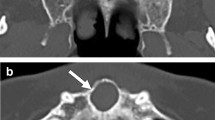

Altogether, 412 patients with maxillary cyst-like lesions (including several benign tumors) were enrolled. All panoramic radiographs were arbitrarily assigned to the training, testing 1, and testing 2 datasets of the study. The deep learning process of the training images and labels was performed for 1000 epochs using the DetectNet neural network. The testing 1 and testing 2 images were applied to the created learning model, and the detection performance was evaluated. For lesions that could be detected, the classification performance (sensitivity) for identifying radicular cysts or other lesions were examined.

The recall, precision, and F-1 score for detecting maxillary cysts were 74.6%/77.1%, 89.8%/90.0%, and 81.5%/83.1% for the testing 1/testing 2 datasets, respectively. The recall was higher in the anterior regions and for radicular cysts. The sensitivity was higher for identifying radicular cysts than for other lesions.